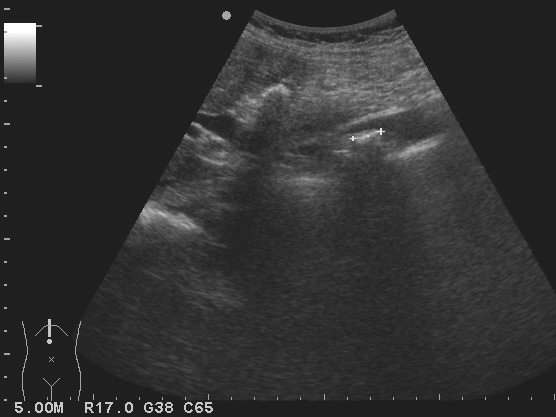

1)胆管腔内存在伴有声影的恒定团状强回声(图2-6-4),个别呈中等或低回声(图2-6-5)。

2)结石的近端胆管由于梗阻出现不同程度扩张。胆管壁增厚,回声增强。胆囊各径可增大,胰管可扩张。

3)团状强回声与胆管壁之间分界清楚,结石周围可见细窄无回声带环绕。

4)脂肪餐或变换体位后观察到结石强回声可发生移动。

5)部分结石由于结构松散、较小或呈泥沙样,可呈中等或较低回声,后方声影不明显。